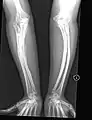

Type V

Having the same clinical features as Type IV, it is distinguished histologically by "mesh-like" bone appearance. Further characterized by the "V triad" consisting of (a) radio-opaque band adjacent to growth plates, (b) hypertrophic calluses at fracture sites, and (c) calcification of the radio-ulnar interosseous membrane.[24]

OI Type V leads to calcification of the membrane between the two forearm bones, making it difficult to turn the wrist. Another symptom is abnormally large amounts of repair tissue (hyperplasic callus) at the site of fractures. Other features of this condition include radial head dislocation, long bone bowing, and mixed hearing loss.